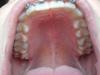

2 месяца 22 дня + лавандовые лигатурки=)

brekets.jpg

3 прием и небольшой отчет за этот красивый срок - 2 месяца и 22 дня=)

1. Поменяли лигатурки и на август они у меня фиолетовые, а точнее лавандовые=) как выразилась ассистентка!

2. Двойка и тройка вроде стали поровнее, но какой-то наклон не тот=( как будто вперед слегка, но надеюсь это временный эффект.

3. Сегодня после последних манипуляций...опять зубки не очень хорошо смыкаются...думаю временно! Читать далее »